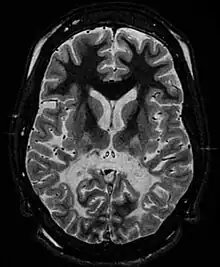

Les leucodystrophies sont des maladies rares caractérisées par un processus de changement démyélinisation du système nerveux central et périphérique, d'apparence primitive et non inflammatoire et aboutissant à une sclérose cérébrale. Ce sont presque exclusivement des maladies génétiques.

Le terme de leucodystrophie se rapporte à un groupe de maladies d'origine génétique affectant la myéline du système nerveux central. La myéline constitue la substance blanche du cerveau et de la moelle épinière. Elle enveloppe la fibre nerveuse de la même manière que l'isolant plastique d'un câble électrique : c'est elle qui permet la bonne conduction des messages nerveux. Dans les leucodystrophies, cette myéline peut avoir des problèmes pour se former ou pour se maintenir (parfois, on remarque une démyélinisation).